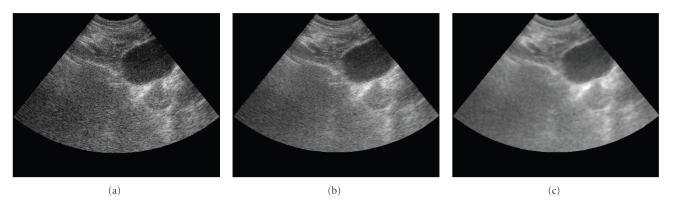

The reconstruction of 3D ultrasound (US) images from mechanically registered, but otherwise irregularly positioned, B-scan slices is of great interest in image guided therapy procedures. Conventional 3D ultrasound algorithms have low computational complexity, but the reconstructed volume suffers from severe speckle contamination. Furthermore, the current method cannot reconstruct uniform high-resolution data from several low-resolution B-scans. In this paper, the minimum mean-squared error (MMSE) method is applied to 3D ultrasound reconstruction. Data redundancies due to overlapping samples as well as correlation of the target and speckle are naturally accounted for in the MMSE reconstruction algorithm. Thus, the reconstruction process unifies the interpolation and spatial compounding. Simulation results for synthetic US images are presented to demonstrate the excellent reconstruction.

从机械配准但位置不规则的B扫描切片重建三维超声(US)图像在图像引导治疗程序中具有重要意义。传统的三维超声算法计算复杂度低,但重建的体积受到严重的斑点污染。此外,当前方法无法从多个低分辨率B扫描重建均匀的高分辨率数据。本文将最小均方误差(MMSE)方法应用于三维超声重建。MMSE重建算法自然地考虑了由于重叠样本以及目标与斑点的相关性而产生的数据冗余。因此,重建过程统一了插值和空间复合。给出了合成超声图像的模拟结果,以证明出色的重建效果。